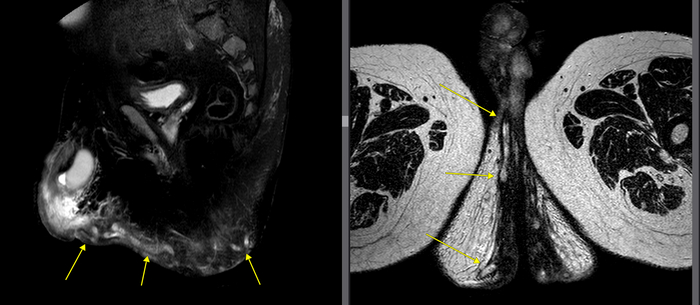

Вид сбоку центрально, вид сверху на уровне анального канала

Для начала мы видим главный свищевой ход, заполненный гноем, который отходит от прямой кишки и идет куда-то в сторону копчика в подкожную область.